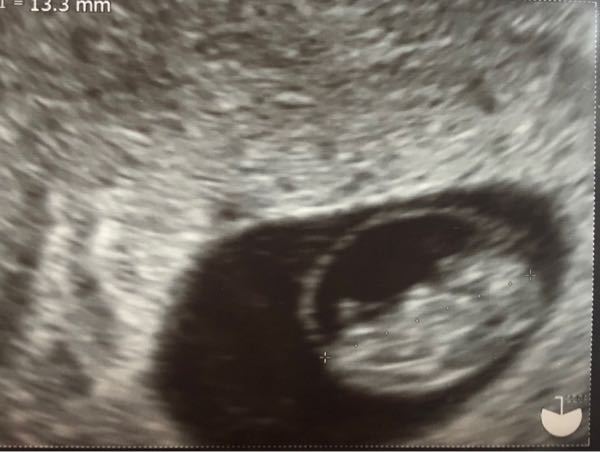

エコー写真なんですが、赤ちゃんの周りの輪っかのようなものは何